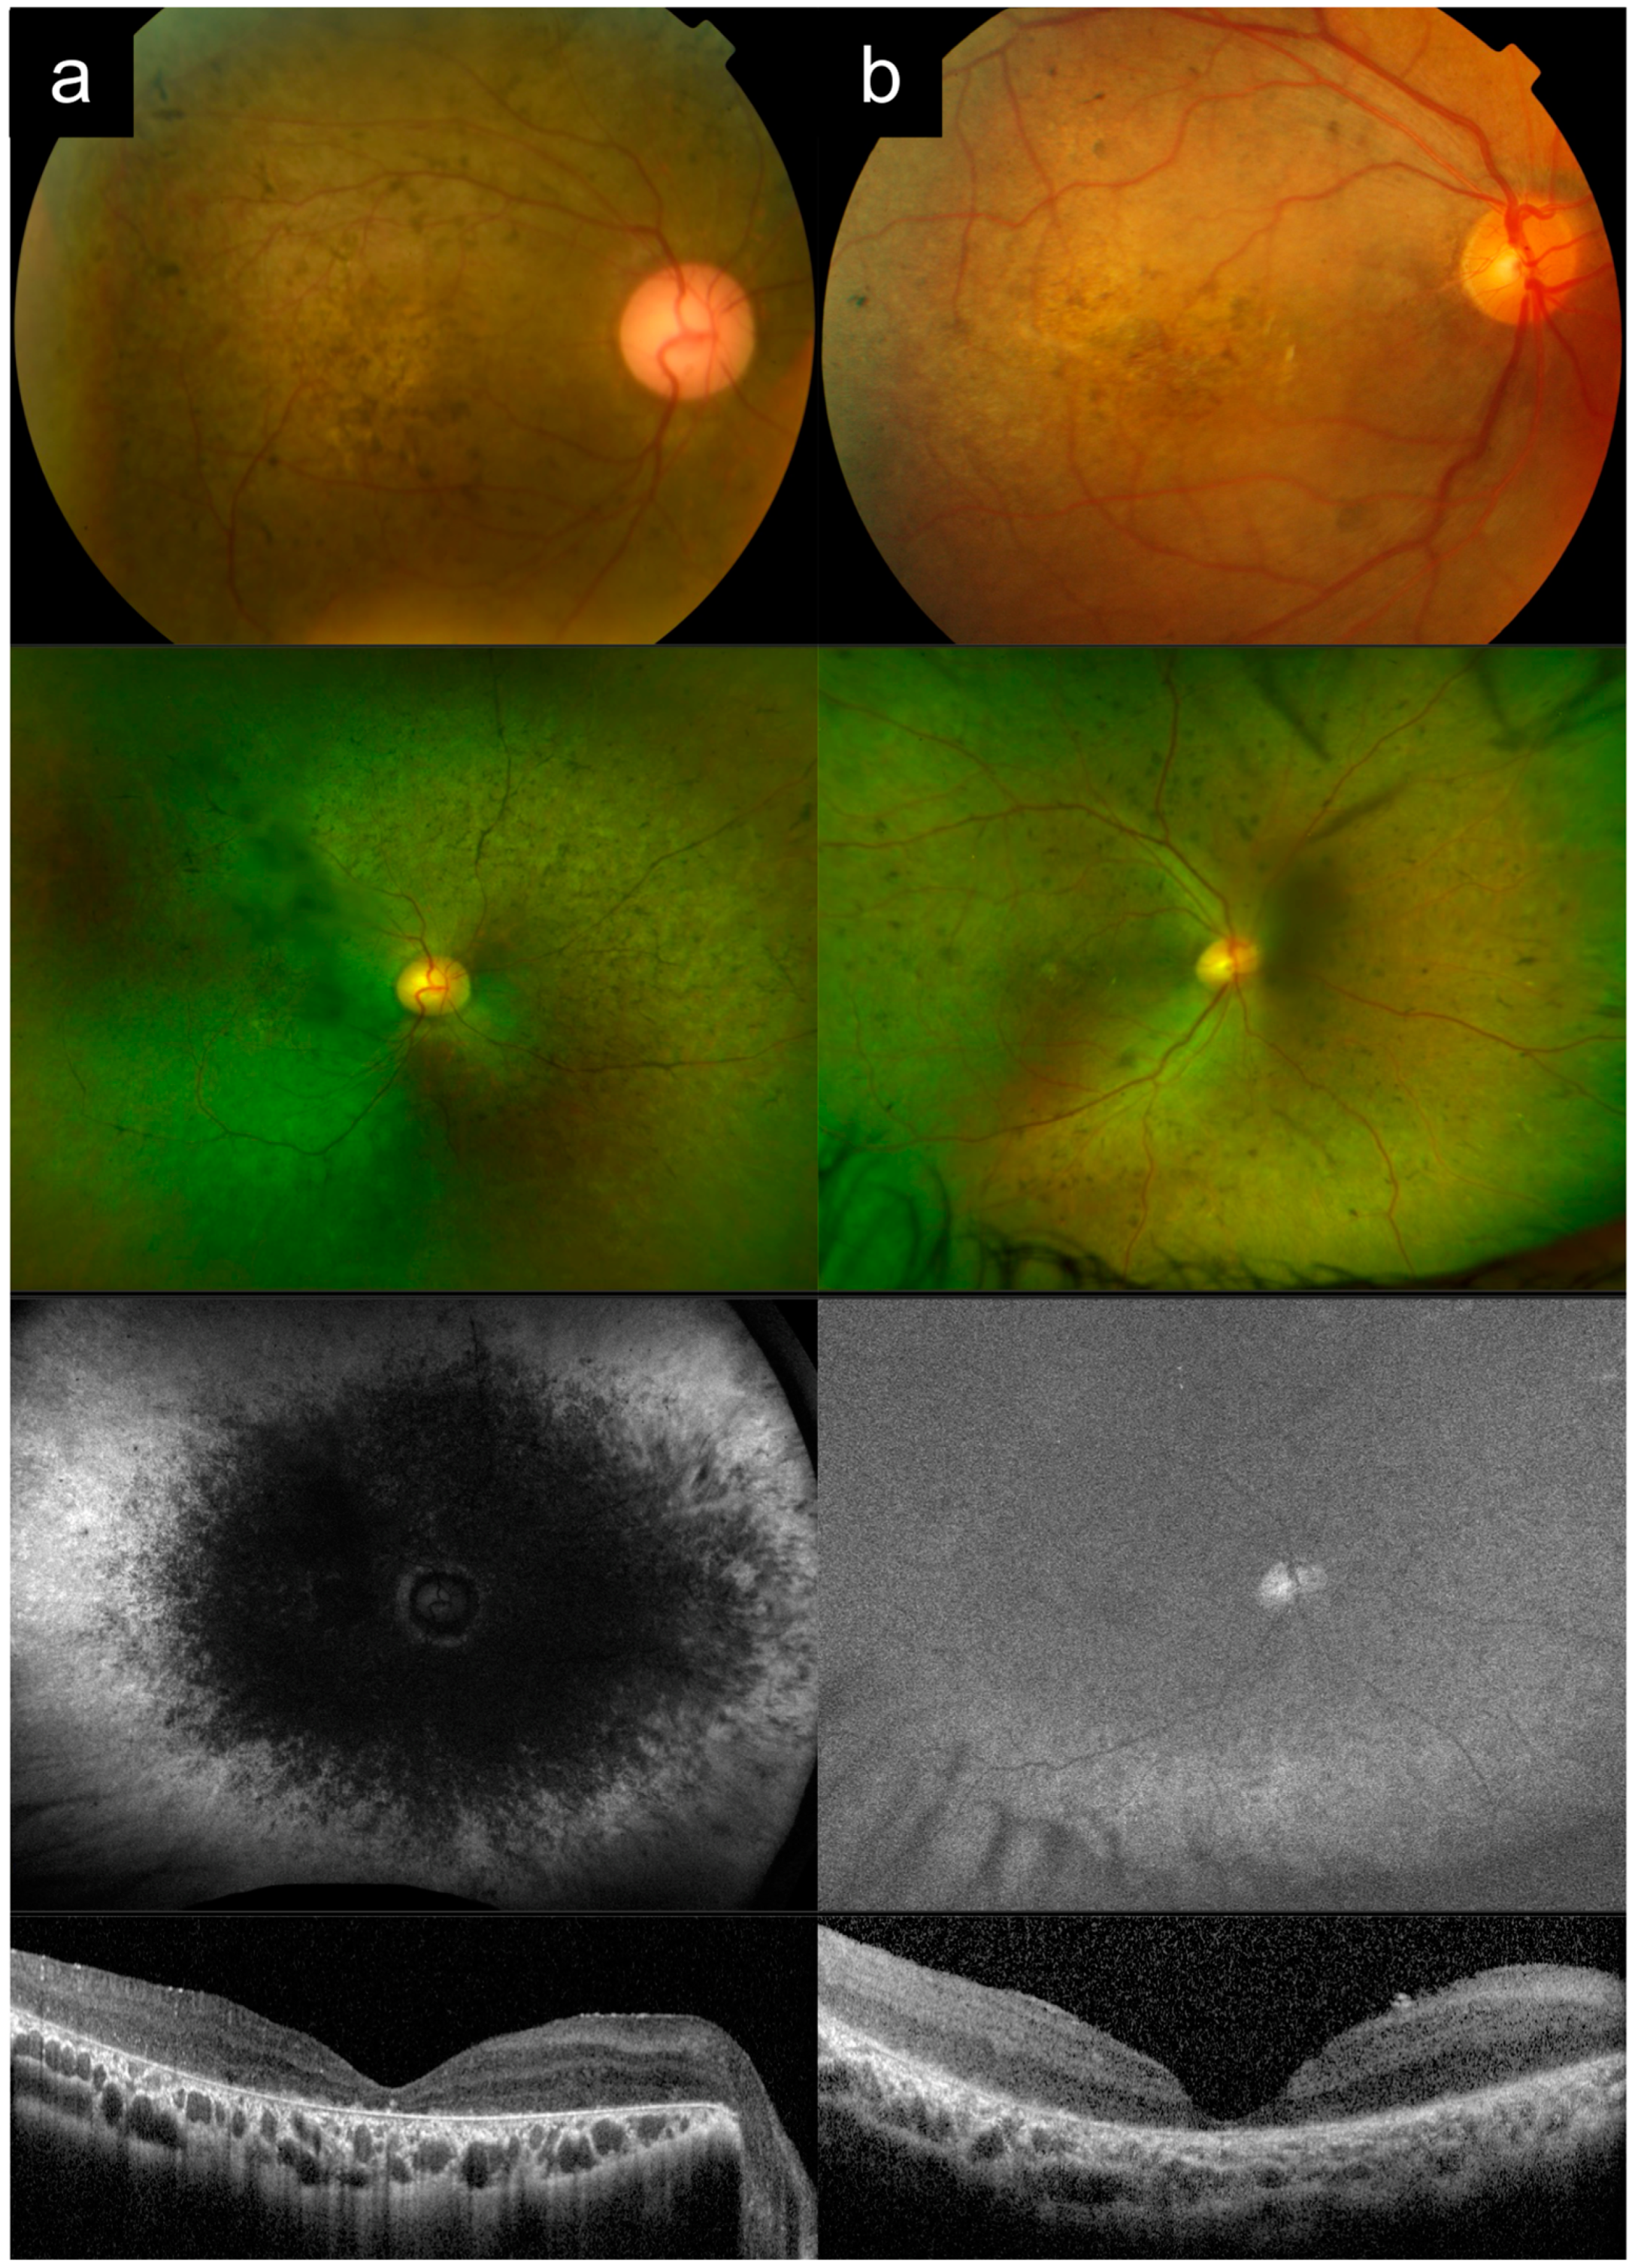

3.1. Cases 1a versus 1b: Typical Adolescent-Onset Stargardt Disease with Macular Atrophy, Flecks, and Peripapillary Sparing Versus PRPH2-Associated Macular Dystrophy

Case 1a presented with bilateral blurred central vision at 15 years of age, which progressively worsened over time. There were no other affected family members, consistent with autosomal recessive (AR) inheritance.

Figure 1a shows multimodal imaging from when the patient was in his 30s. VA in the left eye at that time was 6/45. Fundus examination and CFP imaging showed an area of foveal retinal pigment epithelium (RPE) atrophy with a granular appearance and metallic sheen, surrounded by yellow pisciform flecks distributed throughout the posterior pole and out to the mid-peripheral retina. AF imaging showed a central geographic patch of hypo-AF surrounded by flecks with mixed hyper- and hypo-AF signal. Note the typical sparing of the peripapillary retina, which is more obvious on AF imaging, but also visible on CFP, albeit more subtle. OCT imaging showed outer retinal atrophy and ellipsoid zone (EZ) loss, with patchy choroidal hypertransmission, again with notable peripapillary sparing. Genetic testing revealed two likely pathogenic

Case 1b presented with complaints of persistent blurred vision and mild metamorphopsia in the left eye after uneventful cataract surgery in his late 60s. Best-corrected VA (BCVA) by manifest refraction was 6/7.5.

Figure 1b shows imaging from this time, after his cataract surgery. CFP imaging showed a broad annulus of perifoveal RPE atrophy, with sparing of a small foveal island (explaining the good vision). In the rest of the macula, there were areas of subtle RPE atrophic change, but no frank flecks or yellow subretinal deposits. AF imaging, however, revealed much more apparent fleck-like lesions, although there was no peripapillary sparing. OCT imaging showed perifoveal RPE and outer retinal atrophy, with relative sparing of a small subfoveal region. Prior to genetic testing results, this patient had been diagnosed by multiple specialists as having “late onset Stargardt disease”. Genetic testing subsequently identified the

PRPH2 c.533A>G p.Q178R variant. Pedigree by history revealed that the subject’s mother was also likely affected, which was consistent with an autosomal-dominant (AD) pattern of inheritance.

Case 1a represents a typical phenotype of

ABCA4-RD, presenting with adolescent-onset “classical” Stargardt disease with macular atrophy, flecks, and peripapillary sparing [

16,

24,

25]. Case 1b is a

PRPH2-associated macular dystrophy mimicking Stargardt disease. Key distinguishing features between these two cases are the age of onset, peripapillary sparing, and the inheritance pattern from the pedigree (

Table 2). The younger age of onset in adolescence, presence of clear peripapillary sparing, and the AR inheritance pattern all favor a diagnosis of

ABCA4-RD versus

PRPH2-RD. Note that the yellow deposits or flecks and AF appearance can look very similar in both diseases, as in this case. In addition, the small area of central foveal sparing in Case 1b, though absent in this Case 1a, can also occur in

ABCA4-RD, as in Case 4a later.